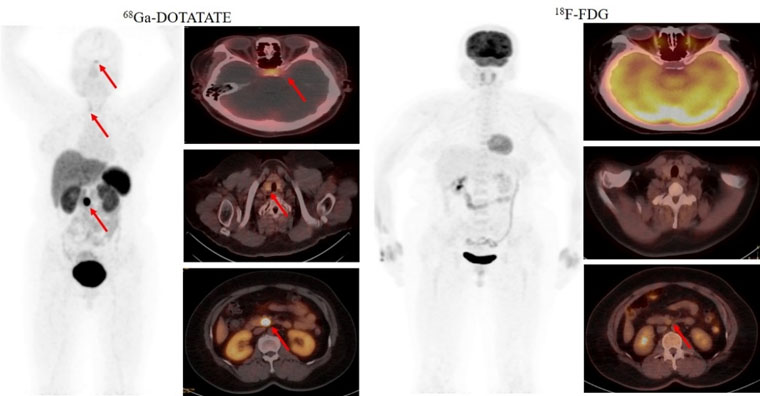

首個病例患者為一名49歲的女性,間斷低血糖超過1年,甲狀旁腺激素檢查異常升高。腦MRI提示為腦垂體微腺瘤,上腹部MRI檢查未發現明顯異常。但臨床懷疑胰腺存在病變,經新探針68Ga-DOTATATE PET/CT檢查,發現了胰腺病灶,綜合診斷多發性內分泌瘤病I型(MEN1型)。經胰腺穿刺病理證實為神經內分泌腫瘤G2。68Ga-DOTATATE及18F-FDG PET/CT雙核素的檢查結果為患者臨床精準診療提供了胰腺病灶的影像學證據。

2021年5月,我院核醫學科率先獲得河北省最高級別的IV類放射性藥品使用證書。在學科帶頭人趙新明教授的帶領下,科室成員汲取全國優秀核醫學科經驗,成功開展了多種新型分子探針PET/CT臨床顯像工作。這些新型分子影像探針包括68Ga-DOTATATE(68Ga-生長抑素受體激動劑,針對神經內分泌腫瘤)、68Ga-JR11(68Ga-生長抑素受體拮抗劑,針對神經內分泌腫瘤)、68Ga-FAPI(68Ga-成纖維細胞活化蛋白抑制劑,針對腫瘤微環境中腫瘤相關成纖維細胞,用于各種腫瘤顯像)和68Ga-PSMA(68Ga-前列腺特異性膜抗原,針對前列腺癌等多種惡性腫瘤)等,新型PET分子探針(顯像劑)的應用對相關腫瘤診斷、分期和療效評價產生了質的飛躍。